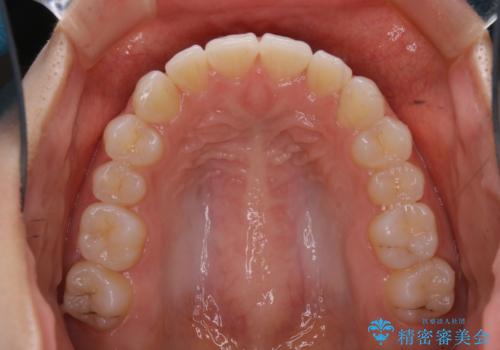

前歯のがたつきをインビザラインで治療

- 上下前歯のがたつきが気になるとの事で来院された患者様です。がたつきの程度が軽度であったため、インビザラインライトにて治療をおこないました。

がたつきの程度が軽度であったことと、インビザラインを正しく装着して頂けたことで短期間で治療終了することが出来ました。